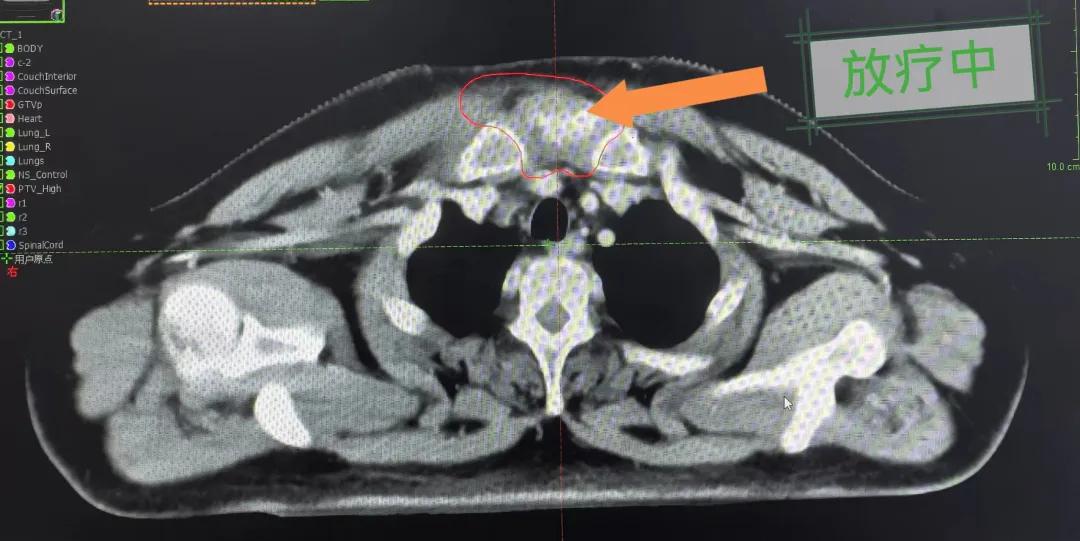

隨后,趙亮主任帶領(lǐng)放療團(tuán)隊(duì)以最快的速度完成了患者的放射治療計(jì)劃,在保證放療精準(zhǔn)打擊腫瘤的同時(shí),利用先進(jìn)的三維立體精確放療技術(shù),最大限度的避免心臟、肺部的損傷發(fā)生,整體治療精準(zhǔn)度達(dá)到1mm以內(nèi)。經(jīng)過(guò)10次的放射治療后,患者疼痛已明顯減輕,胸部腫物肉眼可見(jiàn)的縮小,患者及家屬臉上終于露出久違的笑臉。

治療期間,患者沒(méi)有出現(xiàn)明顯不適,治療結(jié)束后,患者胸壁腫物由最初8cm縮小至約1cm,后患者至外科行手術(shù)治療。